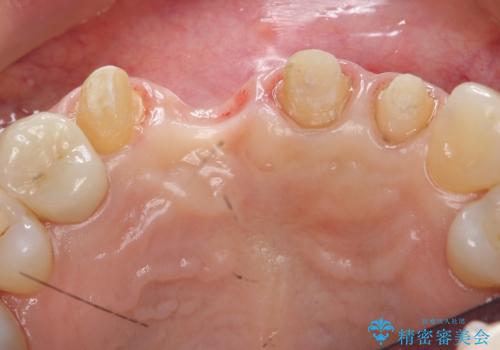

右上1番目の歯は根元まで割れてしまっており、保存不可能だったため抜歯となりました。

抜歯後、骨と歯肉の回復を待ち、オールセラミッククラウンによるブリッジで補綴を行いました。